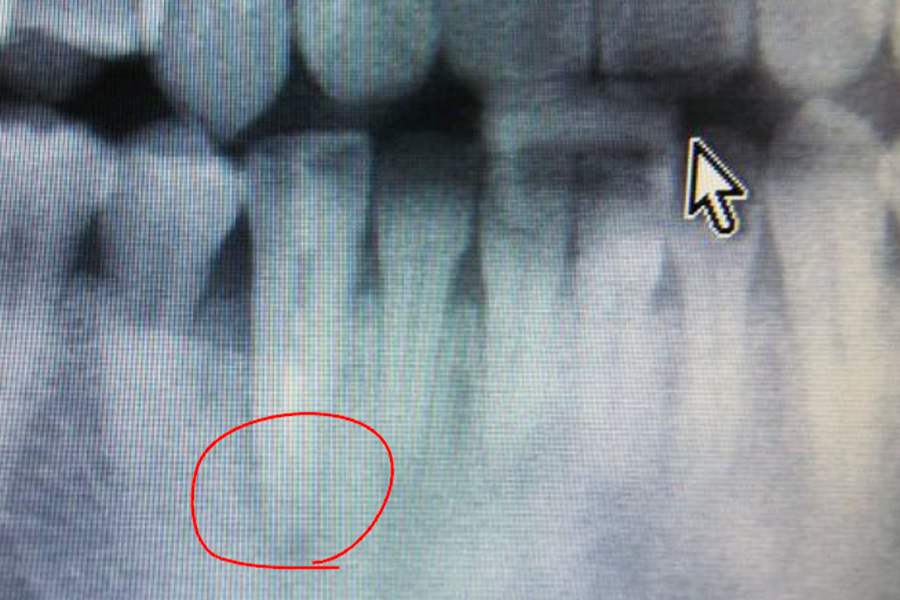

- スプリットクレスト(歯槽堤拡大術)

- 骨が細い為、骨造成が必要となる場合やインプラントの安定が得にくい可能性があるので、定期メンテナンスと自己ケアの両立が大切になります。